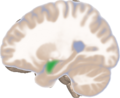

Left lateral view of the amygdala in an average human brain

Amygdala highlighted in green on sagittal T1 MRI images